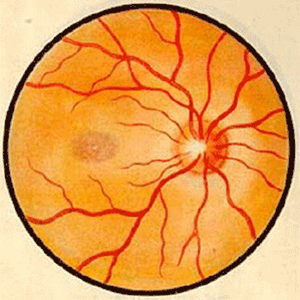

视神经病变

宜昌新利体育中医眼科主任秦大军接连为视神经病变患者医治

新利体育学术资讯:脉络膜新生血管医治 评估的思考